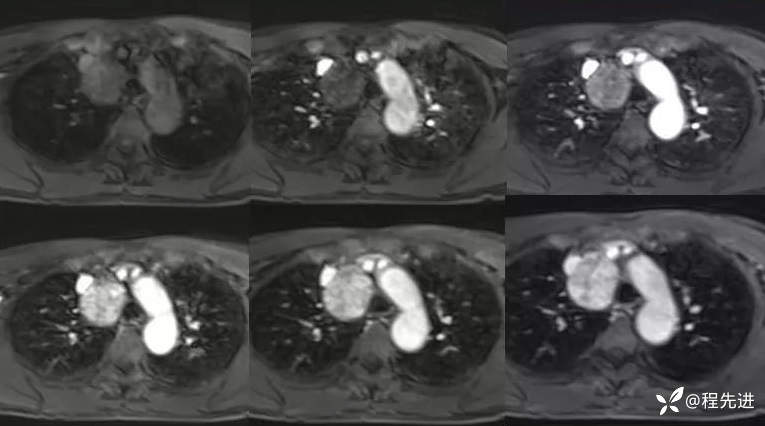

MR

DWI

ADC

T1+C 动脉增强